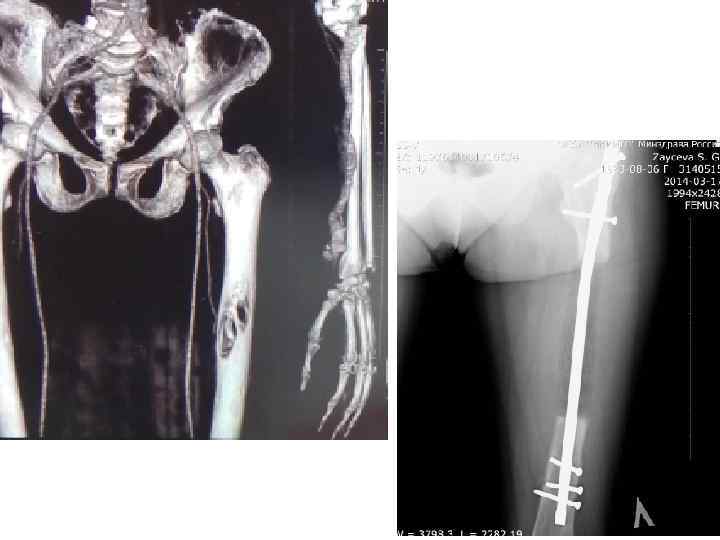

Ортопедическая хирургия реконструкция вертлужной впадины • Напечатанные 3 D модели используются для анализа переломов и определения точного местонахождения и траектории винтов выравнивания и пластин фиксации.